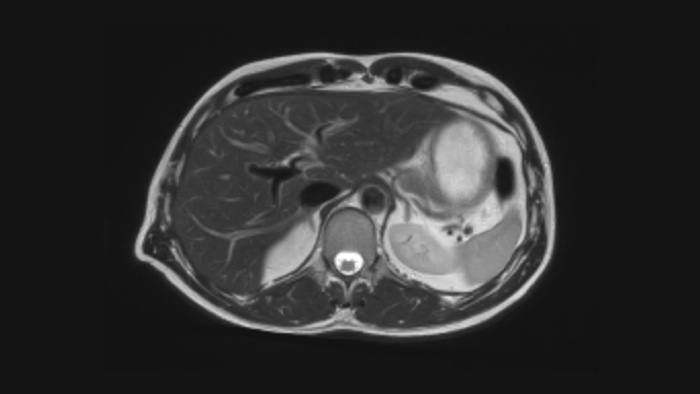

La nouvelle réalité clinique : confiance et rapidité

Vitesse Accélérez vos acquisitions jusqu’à 50 %. Gagnez du temps dans votre planning ou réalisez des séquences supplémentaires pour compléter le diagnostic.2

Confiance diagnostique Jusqu’à 60 % de résolution spatiale supérieure, dans le même laps de temps4, notamment pour les explorations ostéoarticulaires.